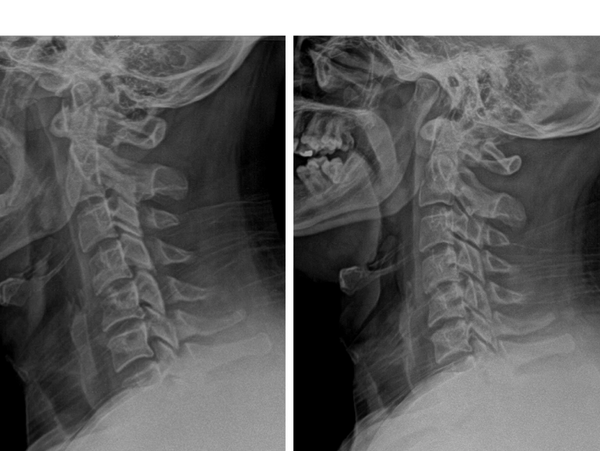

After just 12 visits on our I-TRAC decompression, one patient is already showing noticeable changes in the right direction. His before-and-after X-rays reveal early improvement in the alignment and curvature of his cervical spine. His forward head posture measured 55 mm - reduced to 21 mm. The traction has begun to reduce abnormal forward head posture and restore the natural cervical curve, helping to relieve tension and improve spinal function. This early progress sets a strong foundation for continued improvement in the weeks ahead.